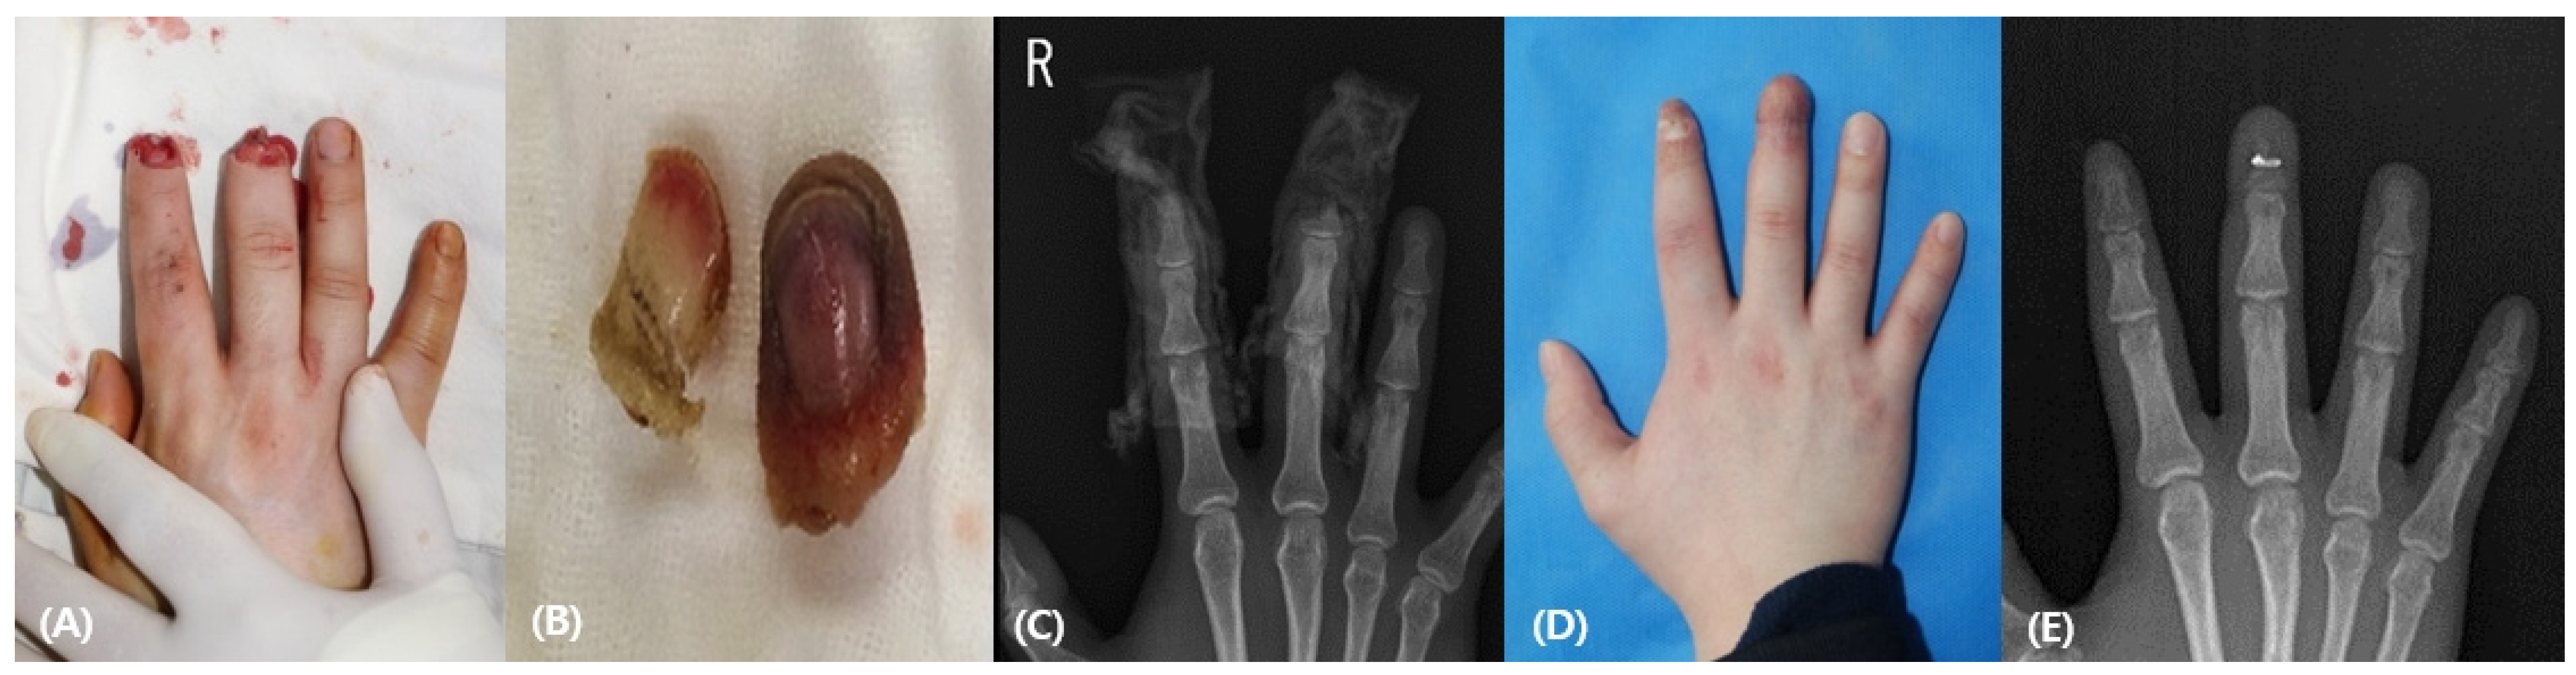

3.1. Case Reports

3.1.1. Patient 1

3.1.2. Patient 2

3.1.3. Patient 3

3.1.4. Patient 4